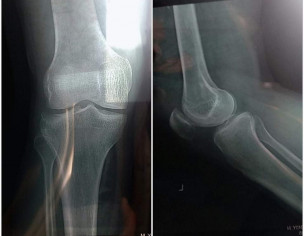

Asking for Wife, Male, 40 years old, Karachi

Mery husband ka accident hogaya ha Fri ko knee fracture hogaya ha Hospital ka nam ne lekh dekhaya tha wahan k doctor ne Kahan kuch nhi ha sojan ha bs Pr pain bht tha to ek or hospital main Dr ko dekhaya wo bol rahy ha fracture ha knee Ab tk 3 doctor ko dekha deya ha 2 bol rahy han fracture ha pr ab pain nhi ha foot b move karaha ha plz ap Bata den k Kya masla ha

Please see a specialist orthopaedic surgeon and your husband might need a CT to look at the bone structure. It is a better modality than MRI for finding small fractures.